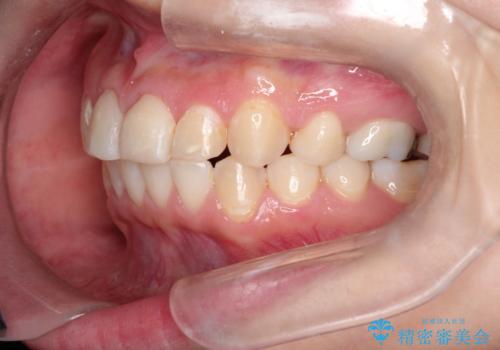

【ワイヤー矯正】前歯が出てるのをなおしたい。

- 前歯の凸凹を主訴に来院されました。

見た目だけではなくかみ合わせも良くなったと満足して頂きました。

治療後は見た目だけでなく、噛みやすくなったと満足していただけました。